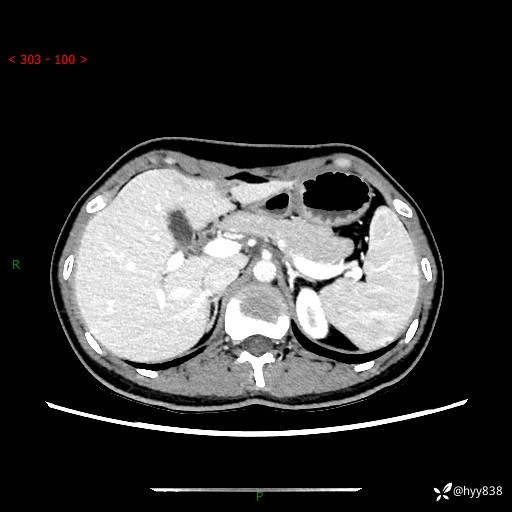

性别:女

年龄:23岁

简要病史:外院发现肝结节,来我院进一步增强确诊

上腹部CT平扫+增强